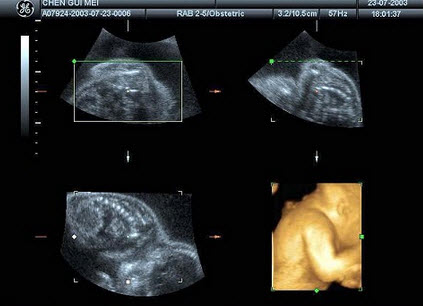

E.胆囊结石并胆息肉,肝转移性癌

根据胎儿四维成像技术,图中结构为()

A.胎儿颜面部

B.胎儿上肢及背部

C.胎儿臀部

D.胎儿下肢

E.胎儿胸部